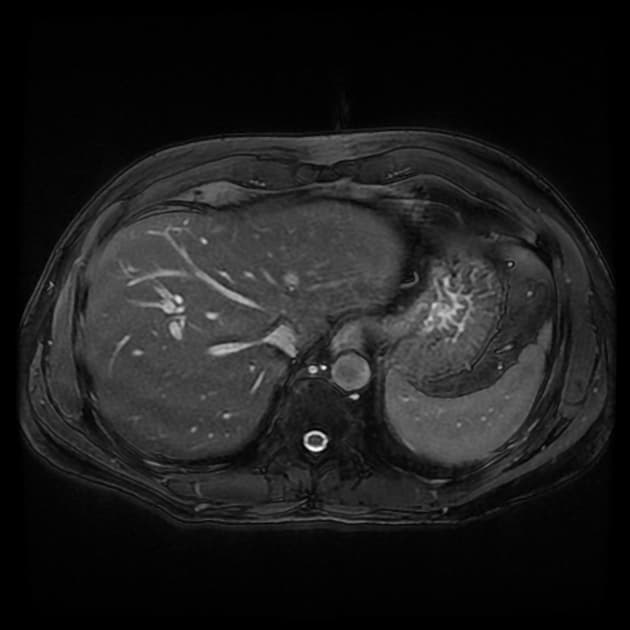

MRCP cho thấy một tổn thương nang nhỏ, ranh giới rõ, xuất phát từ đoạn xa ống mật chủ, ngay phía trên nhú tá Vater, có hình dạng túi thừa và thông trực tiếp với ống mật chủ.

Tổn thương này biểu hiện tín hiệu cao không đồng nhất trên hình ảnh cộng hưởng từ trọng T2 và không có thành phần đặc bắt thuốc trên hình ảnh T1 ức chế mỡ sau tiêm thuốc cản quang.

Không thấy giãn ống mật trong gan hoặc ngoài gan. Ống tụy có đường kính và đi đường bình thường. Túi mật hình dạng bình thường, không dày thành, không có sỏi trong lòng. Ngoài ra, ghi nhận một túi thừa tá tràng nhỏ, tách biệt với tổn thương nang quanh nhú.

Trong trường hợp này, MRCP cho thấy một tổn thương nang nhỏ, ranh giới rõ, xuất phát từ đoạn xa ống mật chủ, ngay phía trên nhú tá Vater, có hình dạng túi thừa rõ rệt và thông trực tiếp với ống mật chủ. Không có giãn ống mật trong gan hoặc ngoài gan đi kèm, và ống tụy có hình dạng bình thường.

Tổn thương biểu hiện tín hiệu cao không đồng nhất trên hình ảnh trọng T2, có thể phản ánh sự khác biệt về thành phần nội dung nang, chẳng hạn như mật đặc hoặc cặn. Hình ảnh sau tiêm thuốc cản quang không thấy thành phần đặc bắt thuốc.